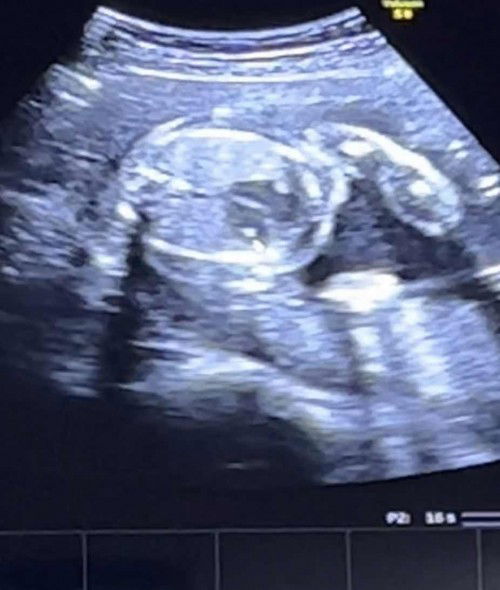

น้อง 22 สัปดาห์ซาวเจอแคลเซียมเกาะที่หัวใจ มีคุณแม่บ้านไหนเจอปหแบบนี้ไหมคะ

กับวลมากค่ะ บ้านไหนเคยเจอปัญหาแบบนี้ไหมคะ เป็นจุดเล็กๆอยู่ฝั่งหัวใจล่างซ้ายค่ะ แต่คุณหมอบอกว่าให้นัดซาวอีกรอบ แต่คือทางนี้เครียดทุกวันเลยค่ะ มันจะหายไปเองใช่ไหมคะ จะหายไปใช่ไหมคะ #ขอบคุณสำหรับคำตอบค่ะ